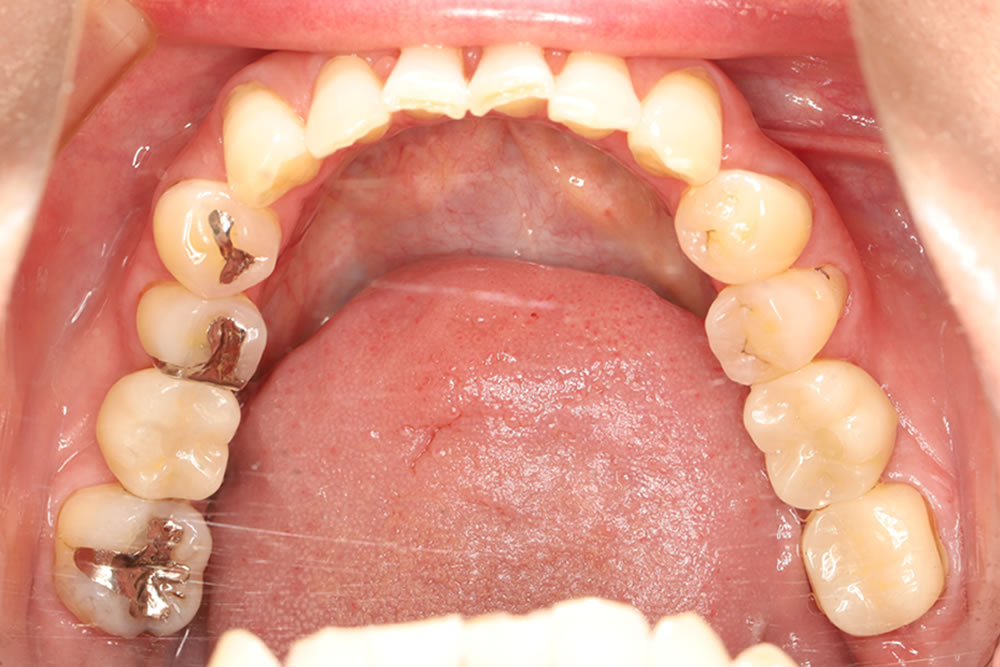

レントゲン上で右下の6番目の根の先端に大きい影が見られます。また左下も噛むと痛みがあるとのことでした。小さい根尖病巣が確認できますが、かなり大きい土台が入っていて再治療が困難な状態なため、患者さまと相談し、右下、左下の大臼歯を抜歯してインプラントで治療する計画を立てました。